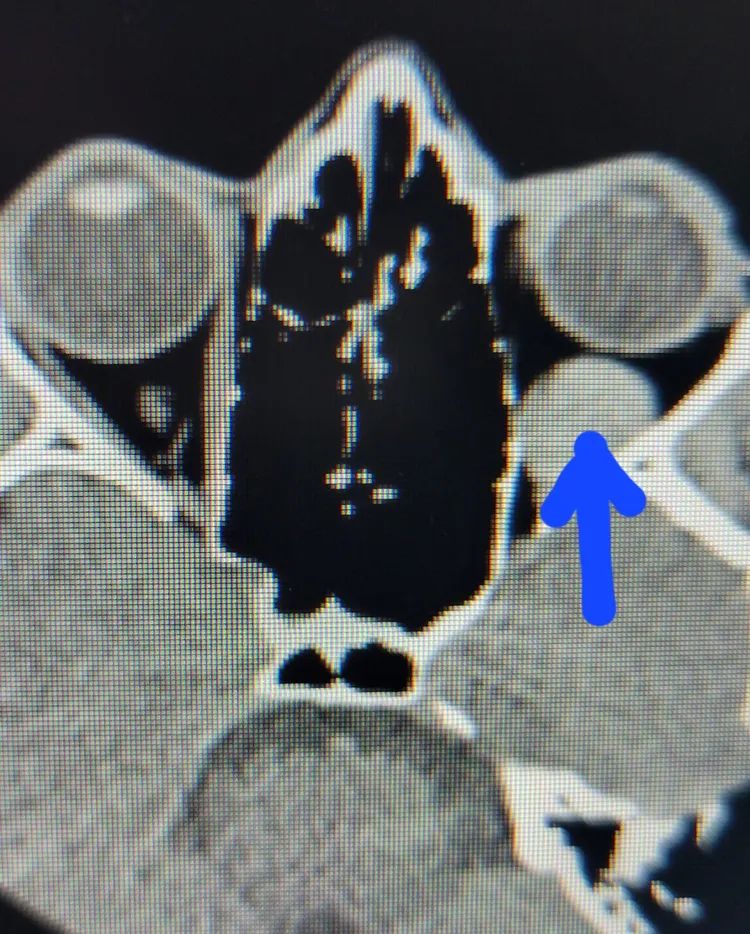

由於左眼嚴重的血腫,眼球根本無法轉動,陳小姐看物體呈現複視,走路時不平衡,容易跌倒,左眼視力也從0.8降0.4,洪啟庭為她安排電腦斷層,竟發現一塊很大的血塊恰在左眼球後方,因此壓迫部分眼外肌,使眼球肌肉運動受限,才有左眼無法轉動形成複視,另可能輕微壓迫視神經,使視力下降。